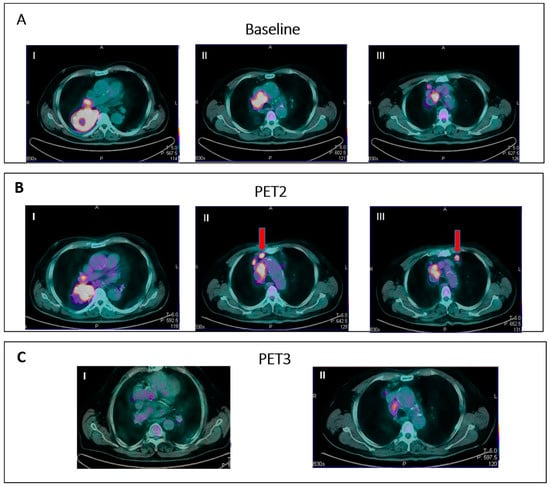

- IR(2): Appearance of new lesions in the context of overall TB stability (Figure 2).